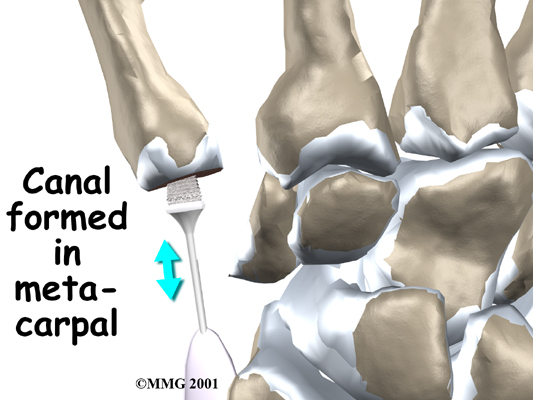

A burr (a small cutting tool) is used to make a canal into the bones that form the thumb joint. The surgeon sizes the stem of the prosthesis to ensure a snug fit into the canal and inserts it. When the new joint is in place, the surgeon wraps the joint with a strip of nearby tendon. This gives the new implant some added protection and stability.

A burr is used to make a small notch, or canal, in the ends of the two bones. The surgeon shapes the notch so the ball-shaped implant will fit snugly in the joint. The implant is placed between the ends of the shaped bones.

View animation of of canal formation